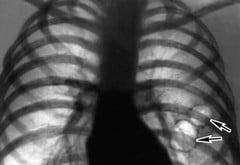

Буллезная эмфизема легких

Считается, что буллезная эмфизема легких — это проявление наследственных либо генетических отклонений. Что касается этиологии и патогенеза этой формы, то они пока еще до конца не выяснены.

Буллезная эмфизема легких характеризуется образованием воздушных пузырьков различных размеров (булл), которые локализуются, как правило, в краевых отделах легких. Эти пузырьки могут быть единичными, множественными, распространенными или локальными. Их размеры колеблются от 1 до 10 сантиметров. Данный тип заболевания имеет одну особенность — раннее развитие дыхательной недостаточности. Она развивается не только из-за самой эмфиземы, но и за счет сдавливания окружающей здоровой ткани буллами. Работа участка с пузырьками резко нарушается. Симптоматика является тяжелой и опасной.